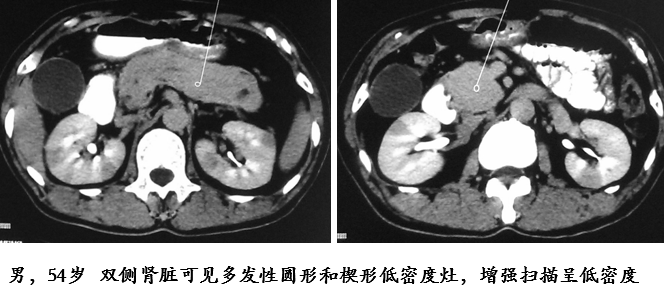

肾脏受累

肾脏受累治疗后